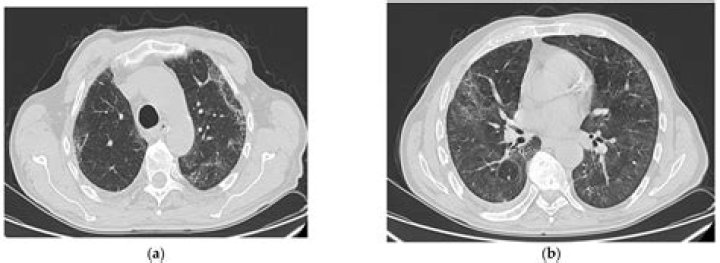

Does pulmonary fibrosis show up on a CT scan?

For some types of pulmonary fibrosis, the results from a CT scan can be very clear and allow a diagnosis to be made. For example, on a CT scan IPF often shows up as a distinctive pattern on the lungs. You might hear your doctor call this honeycomb lung.